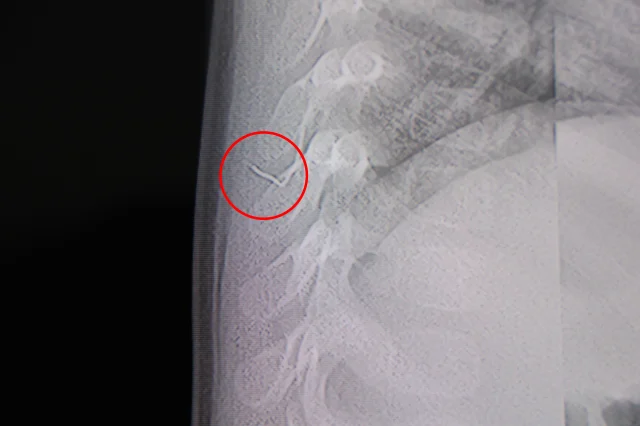

2 SANTİMETRELİK ZIMBA TELİ ÇIKARILDI

Hasta, genel anesteziye alınmadan, lokal anestezi ve sedasyon eşliğinde ameliyata alındı. Yapılan müdahalede yabancı cisim tamamen çıkarıldı. Çıkarılan cismin, ince zımba teline benzer metal bir tel olduğu ve yaklaşık 2 santimetre uzunluğunda bulunduğu tespit edildi. Hasta, aynı gün taburcu edildi.

Konuya ilişkin açıklama yapan Beyin ve Sinir Cerrahisi Uzmanı Prof. Dr. İdris Altun, "Sırtında yabancı bir cisim olduğu söylenmiş ancak çıkarılamayacağı ve 8 yaşına kadar beklenmesi gerektiği ifade edilmişti. Bize başvurduğunda yaptığımız tetkiklerde, cilt altında, omurilik kanalına çok yakın ve akciğer zarına doğru ilerleyen bir yabancı cisim tespit ettik. Hastamızı tamamen uyutmadan, lokal anestezi ve sedasyon eşliğinde müdahale ederek lezyonu tamamen çıkardık. Çıkardığımız cismin ince zımba teline benzer, yaklaşık 2 santimetre uzunluğunda metal bir tel olduğunu gördük. Bu yabancı cisim alınmasaydı, bölgede enfeksiyon gelişebilirdi. Enfeksiyon sonucu omurilik kanalında ciddi hasarlar oluşabilir, çocuk büyüdükçe cismin hareket etmesine bağlı olarak omurilikte zedelenmeler meydana gelebilirdi. Ayrıca yana doğru ilerleyerek akciğer zarına ve akciğere batma riski vardı. Bu da enfeksiyona ve ilerleyen süreçte tümörle karışabilecek tablolara neden olabilirdi. Şu an hastamız gayet sağlıklı. Gerekli kontrolleri yaptık ve aynı gün taburcu ettik" dedi.